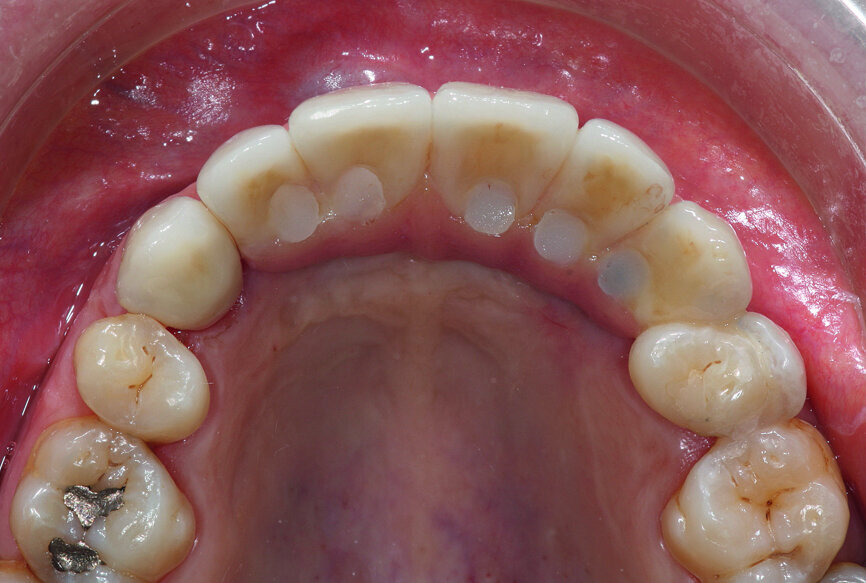

At the age of 28, the patient was involved in a traffic accident, which resulted in significant trauma to her maxilla, including the loss of her central and lateral incisors and left canine. The shock also led to the loss of alveolar bone in the same area. The first premolars were absent, probably owing to previous orthodontic treatment.

The original treatment consisted of placing two implants in the residual bone and an anchorage reinforcement screw-retained bridge to maintain a removable prosthesis, which included five teeth and a large false gingiva (Fig. 1).

Dissatisfied with the treatment, the patient was re-examined three years after the initial treatment. The patient’s smile showed an infiltration at the right lateral incisal level and that the prosthetic teeth were placed off-centre. The lip support, ensured by a large false gingiva, was correct. The cosmetic material of the right maxillary canine was fractured (Figs. 1 & 2).

Once the patient’s prosthesis had been removed and an examination of the site conducted, an extremely negative prognosis was determined for the implants (Fig. 3), which is often the case with maxillary overdentures. The right implant showed a loss of the majority of its vestibular bone, causing significant recession. The tissue was hyperplastic, making hygiene difficult. The framework was off-centre presumably because of the implants, which explained the off-centre axis of the prosthetic teeth.